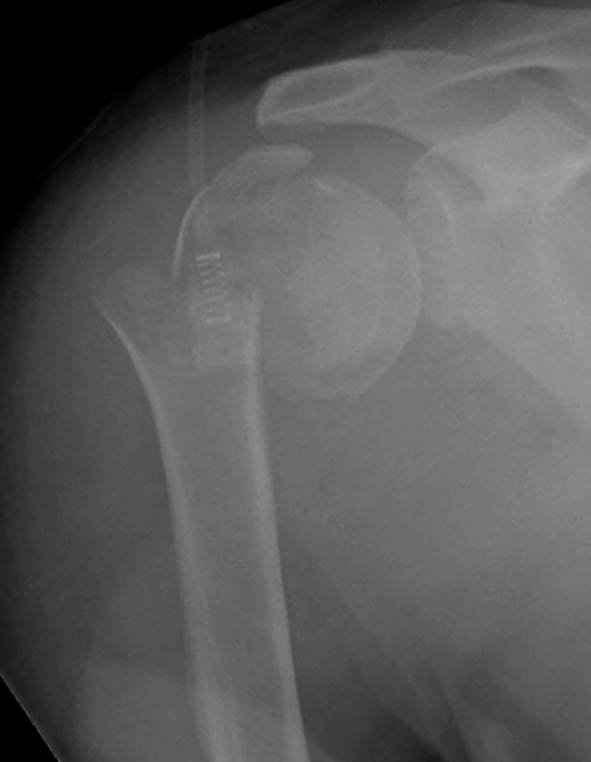

Наш недавний случай перкутанной фиксации "методом

Сиэтла" спицами 2.8 мм с резьбой на конце.

Головка плечав небольшом варусе или это проекционное?

На 20-е сутки снял гипс, одел фиксирующюю

ортопедическую повязку. Вот контроль. Как видно, стояние хорошее, уже формируется костный мозоль.

Думаю еще недели 3 продолжать фиксацию.

-Головка плеча в небольшом варусе или это

проекционное?

Да, там имеем небольшой варус, надеемся, что в будущем проблемы не будет.

Из-за большого обьема конечности доступ к бугорку был затруднен, предварительно зафиксированный шуруп не удержал бугорок, поэтому фиксацию провели толстыми нитками. Состоятельность фиксации бугорка обычно проверяем во время операции, под рентген контролем проводится движения конечности, особенно приведение.